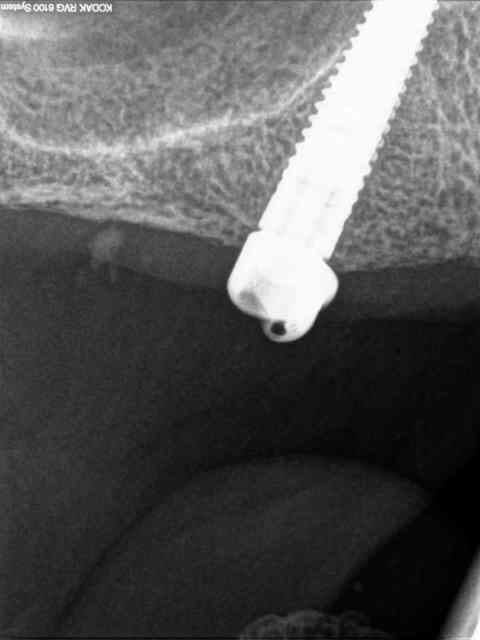

secteur 2:

on voit bien ici que cette méthode reste suffisamment précise pour longer le sinus sans le pénétrer.

je n'en demande pas d'avantage.

Cet implant pénètre de 5 à 6 mm dans le sinus.